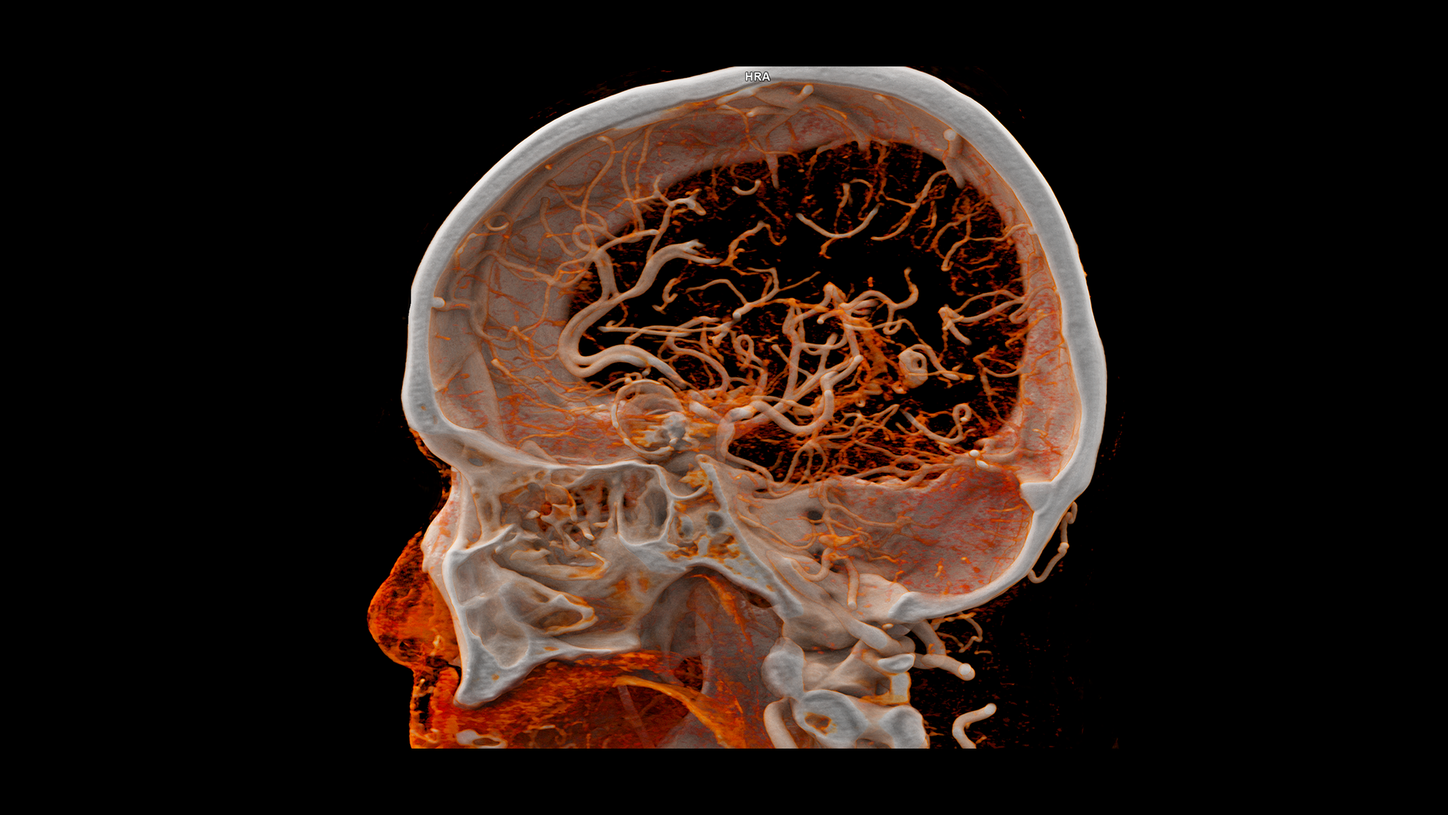

At the heart of NAEOTOM Alpha® is a radically new photon-counting detector. The QuantaMax detector directly converts X-rays into an electrical signal, which is then used to create an image. The energy of each X-ray is measured, so spectral information is available for every scan, and the images are contrast-rich with high spatial resolution at the same dose. Combining the high spatial resolution of the QuantaMax photon-counting detector with our Dual Source temporal resolution enables the visualization of fine details for increased diagnostic confidence.

QuantaMax, the first photon-counting detector, overcomes the limitations of conventional CT detectors by providing data at high spatial resolution, without electronic noise and with improved contrast-to-noise ratio.

The unique Dual Source technology enables a native temporal resolution of 66 ms and a scan speed of up to 74 cm/sec – mastering even the most challenging imaging tasks.